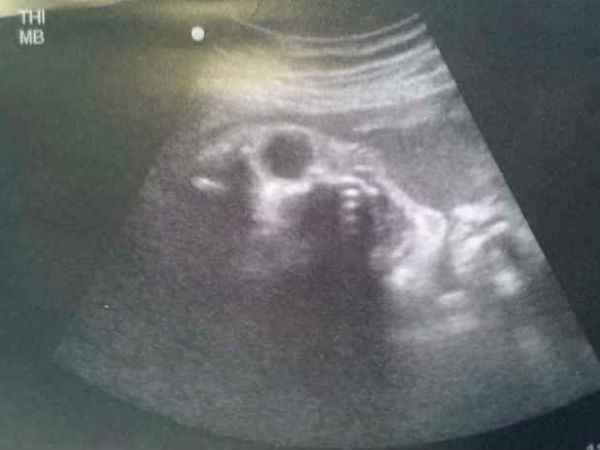

ಭಯ ಹುಟ್ಟಿಸುವ ಆ ಅಲ್ಟ್ರಾಸೌಂಡ್ ಸ್ಕ್ಯಾನ್ ಚಿತ್ರಗಳು!!

ತಾನು ಗರ್ಭಿಣಿ ಎಂದು ಅರಿವಾದ ಕ್ಷಣದಿಂದಲೇ ತಾಯಿಯಾಗುವವಳಿಗೆ ತನ್ನ ಒಡಲಿನ ಮಗುವಿನ ಬಗ್ಗೆ ವಾತ್ಸಲ್ಯ ಮೂಡತೊಡಗುತ್ತದೆ. ಈ ಮಗುವಿನ ಮುಖ ಹೇಗಿರಬಹುದು ಎಂಬ ಕುತೂಹಲ ತಣಿಸಲು ಒಂಭತ್ತು ತಿಂಗಳ ದೀರ್ಘ ಕಾಲ ಕಾಯುವುದು ಅನಿವಾರ್ಯ. ಆದರೆ ಇಂದಿನ ವಿಜ್ಞಾನ ಗರ್ಭದಲ್ಲಿರುವ ಮಗುವಿನ ಆರೋಗ್ಯ ಹಾಗೂ ಆಕಾರವನ್ನು ಕಂಡುಕೊಳ್ಳಲು ಅಲ್ಟ್ರಾಸೌಂಡ್ ತಂತ್ರಜ್ಞಾನವನ್ನು ಬಳಸುತ್ತಿದೆ.

ಶಬ್ದದ ಅಲೆಗಳ ಪ್ರತಿಫಲನವನ್ನು ಗ್ರಹಿಸಿ ಕಂಪ್ಯೂಟರ್ ಪರದೆಯ ಮೇಲೆ ತ್ರಿಕೋನಾಕೃತಿಯ ಆಕಾರದೊಳಗೆ ಗರ್ಭದಲ್ಲಿರುವ ಮಗುವಿನ ಆಕಾರ ಹಾಗೂ ಇತರ ಮಾಹಿತಿಗಳನ್ನು ವೈದ್ಯರು ಗಮನಿಸಿ ಸೂಕ್ತ ಚಿಕಿತ್ಸೆ ನೀಡುತ್ತಾರೆ. ಈ ಚಿತ್ರವನ್ನು ಗರ್ಭಿಣಿ ಸಹಾ ನೋಬಹುದಾದುದರಿಂದ ತನ್ನ ಮಗುವಿನ ಮುಖ ಹೇಗಿರಬಹುದು ಎಂಬ ಕುತೂಹಲ ಆಕೆಯಲ್ಲಿ ಕೊಂಚ ಭಯವನ್ನೂ ಹುಟ್ಟಿಸಿರುತ್ತದೆ.

ಒಂದು ವೇಳೆ ಇಲ್ಲಿ ಮುದ್ದುಮಗುವಿನ ಮುಖದ ಬದಲು ಭಯಾನಕ ಆಕಾರ ಕಂಡುಬಂದರೆ? ಹೆದರಿಕೆಯಾಗುತ್ತದೆ ಅಲ್ಲವೇ? ಕೇವಲ ಕಲ್ಪಿಸಿದ ನಮಗೇ ಹೀಗಾದರೆ ಆ ಆಕಾರವನ್ನು ಕಂಡ ತಾಯಿಗೆ ಹೇಗಾಗಬೇಡ? ಇಂತಹ ಕೆಲವು ಅಚ್ಚರಿಯ ಮತ್ತು ಭಯ ಹುಟ್ಟಿಸುವ ಅಲ್ಟ್ರಾಸೌಂಡ್ ಚಿತ್ರಗಳನ್ನು ನೋಡೋಣ...

ಚಿತ್ರ#1 ಅನ್ಯಗ್ರಹದ ಮಗುವೇ ಇದು?

ಈ ಚಿತ್ರದಲ್ಲಿ ಕಾಣುವ ಮಗುವಿನ ಚಿತ್ರ ಯಥಾವತ್ತಾಗಿ ಒಂದು ಅನ್ಯಗ್ರಹ ಜೀವಿಯ ಮುಖದಂತೆ ಕಾಣುತ್ತಿದೆ ಅಲ್ಲವೇ? ಇದು ಎಷ್ಟು ನಿಜವಾಗುತ್ತದೆ ಎಂಬುದನ್ನು ಹೆರಿಗೆಯ ಬಳಿಕವೇ ಖಚಿತಪಡಿಸಬೇಕಷ್ಟೇ. ಈ ಮಗು ಎಲ್ಲರಂತೆ ಮುದ್ದು ಮುಖವನ್ನೇ ಹೊಂದಿರಲಿ ಎಂದು ನಾವೆಲ್ಲಾ ಹಾರೈಸೋಣ. ಈ ಚಿತ್ರವನ್ನು ಯಾವಾಗ ಮಹಿಳೆಯ ಸದಸ್ಯರೊಬ್ಬರು ತೆಗೆದು ಸಾಮಾಜಿಕ ತಾಣದಲ್ಲಿ ಪ್ರಕಟಿಸಿದರೋ, ಆಗಿನಿಂದ ಲಕ್ಷಾಂತರ ಮೊಬೈಲುಗಳಲ್ಲಿ ಇದು ಹರಿದಾಡುತ್ತಿದೆ.